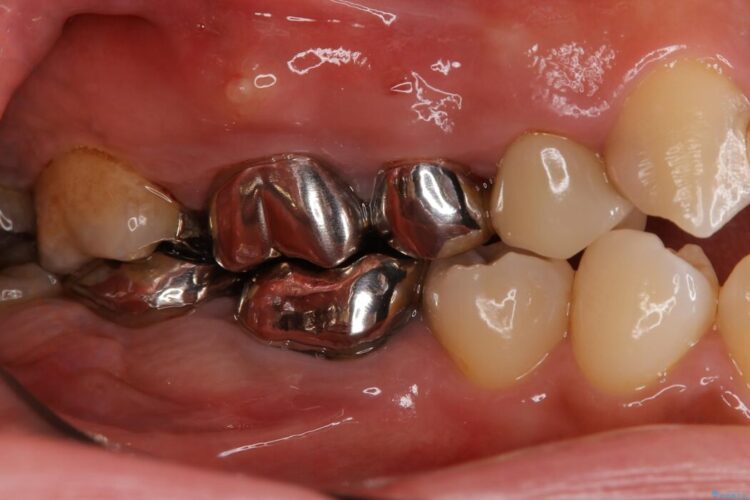

【40代男性】銀歯をセラミックにやり替え

【40代男性】銀歯をセラミックにやり替え ビフォー 【40代男性】銀歯をセラミックにやり替え アフター

銀歯をセラミックにやり替えたいとご来院された患者様です。